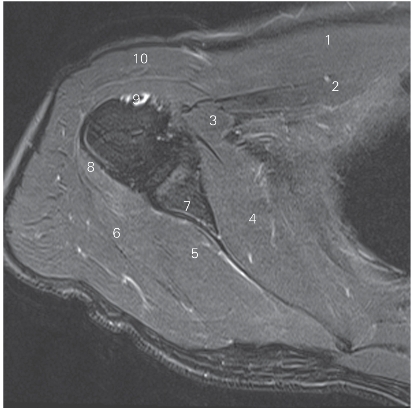

图4-19 经肩峰的矢状断层MR T2WI FS

1 冈上肌 supraspinatus 2 肩峰 acromion

3 冈下肌 infraspinatus 4 肱骨头 head of humerus

5 肱骨大结节 greater tubercle 6 小圆肌 teres minor

7 三角肌 deltoid 8 肱三头肌 triceps brachii

9 肱二头肌 biceps brachii 10 胸大肌 pectoralis major

11 肱骨小结节 lesser tubercle 12 肩胛下肌 subscapularis